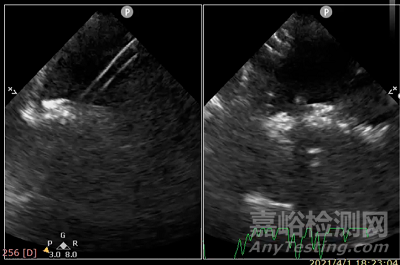

ReAces在開展臨床前動(dòng)物實(shí)驗(yàn)中,完成35頭豬體內(nèi)封堵器植入。取材解剖顯示45天即已內(nèi)完全皮化。通過動(dòng)物試驗(yàn)發(fā)現(xiàn)封堵器再穿操作性良好,植入ReAces 2個(gè)月后成功對(duì)豬房間隔進(jìn)行再穿刺,8.5F房間隔穿刺鞘穿過封堵器中央房間隔后,可將14F輸送鞘送入左房。

主體保持了傳統(tǒng)封堵器“雙盤一腰”的基本結(jié)構(gòu)及工作原理,以保證封堵安全有效。且封堵器中央?yún)^(qū)無金屬物、單層阻流膜設(shè)計(jì),在阻斷血流通過封堵器的同時(shí),由于阻流膜較薄,不會(huì)形成肥厚增生組織,使得從封堵器中穿刺送入鞘管簡(jiǎn)單可行。